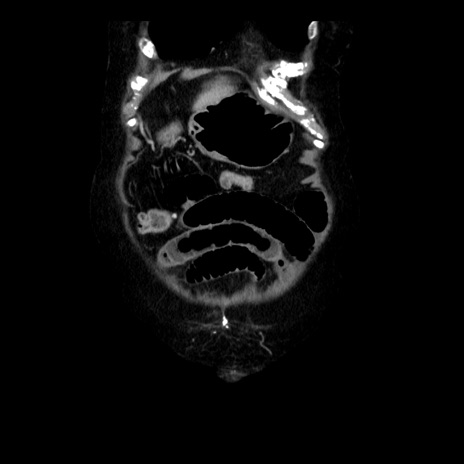

横断像

【症例】 90歳代女性

【主訴】 腹痛・嘔吐

【現病歴】今朝から左側腹部痛を認めた。 経過観察していたが、嘔吐を認めたため来院。

【既往歴】 子宮癌術後

【身体所見】 意識清明、BP 127/54mmHg、P 98bpm Sp02 95%(RA)、BT 35.8°C、腹部平坦・軟腸ぜん動音聴取良好、右下腹部圧痛(+) 反跳痛なし

【データ】WBC 9800、CRP 0.46